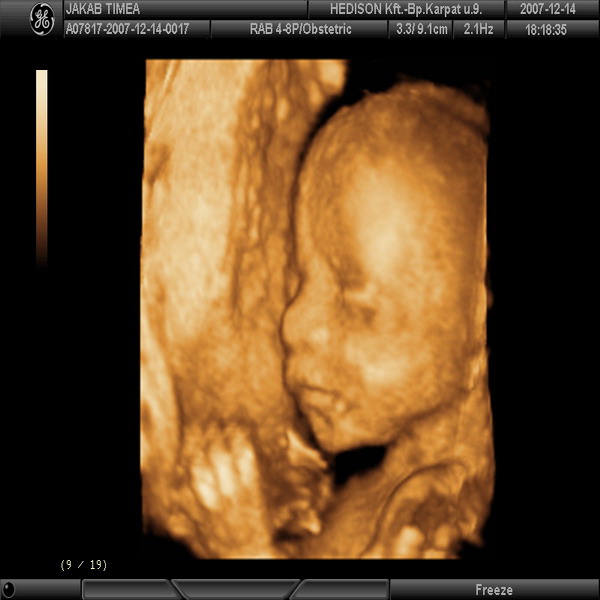

Egyik kedvencem: a kis Bruce Willis:-)